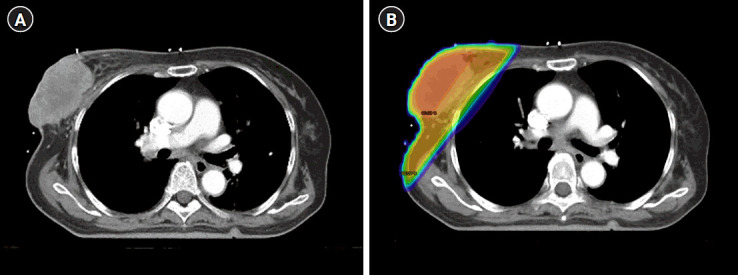

Materials and methods: This retrospective study included patients who received palliative RT of the breast or chest wall for breast cancer with skin involvement. Progression-free survival, freedom from local progression (FFLP), and symptomatic response were evaluated. The prescribed dose to tumor was calculated as the biologically effective dose (BED) using α/β of 4. Symptomatic responses were evaluated until 6 months after RT.

Results: Of the 43 patients included in this study, 48 Gy in 15 fractions was the most common regimen, and the median BED was 86.4 Gy (range, 24.0 to 120.0). With a median follow-up of 15.1 months (range, 1.6 to 63.5), the median FFLP and progression-free survival were 8.4 and 3.6 months, respectively. The 1-year FFLP rates in patients who received BED >75 Gy and BED ≤75 Gy were 78.3% and 49.7%, respectively (p = 0.046). Within 6 months after RT, 75% of patients showed relief of discharge, 67% showed relief of bleeding, and 37% showed relief of pain. There was no grade 3 or higher skin toxicity or other adverse events.

Conclusion: Palliative RT is a safe and effective treatment option for patients with breast cancer with skin involvement, providing symptomatic relief. The administration of BED ≥75 Gy can offer a benefit in achieving durable local control.